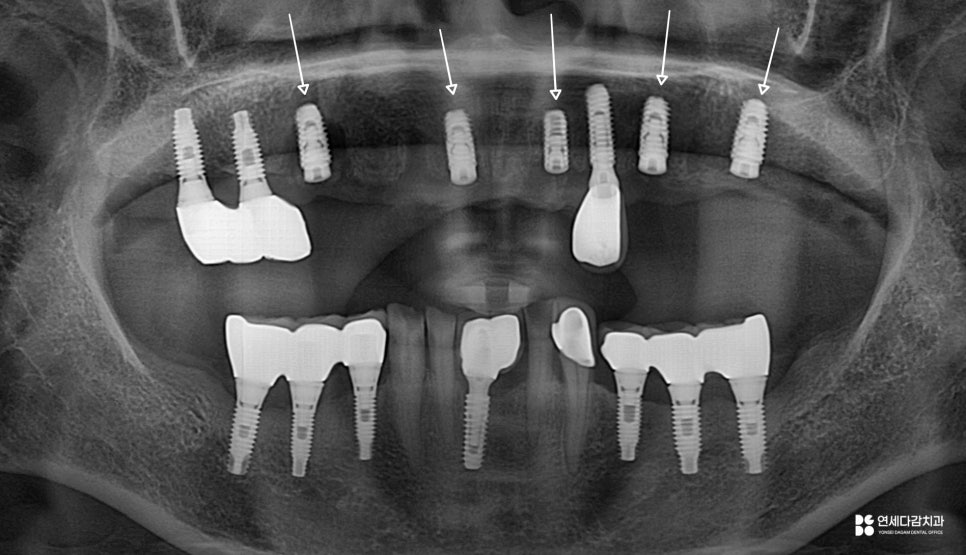

26.01.10

식립 과정이 마무리되면

일정 기간의 골유착을 기다립니다.

픽스처가 뼈와 단단히 결합하기까지

보통 수개월의 시간이 필요하며

골유착이 충분히 이루어진 뒤

보철을 체결합니다.

이렇게 기능, 심미성은 회복이 되며

앞으로의 수명은 사후 관리에 달려있죠.